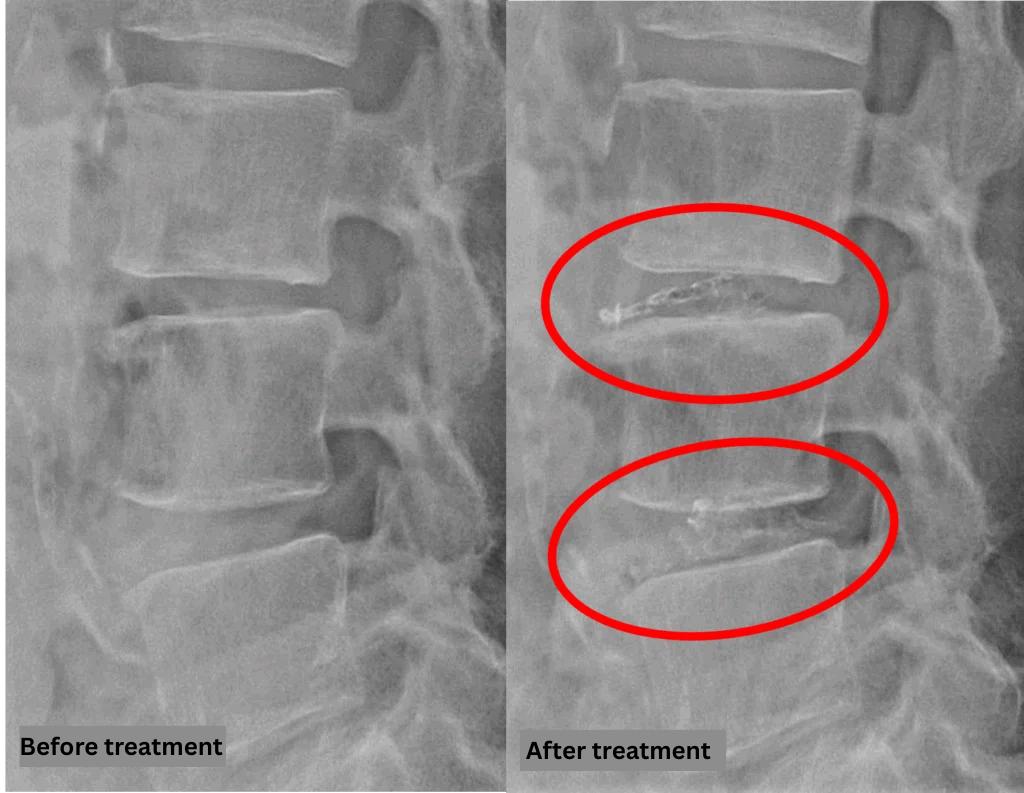

- L2/3, L5/S: Disc degeneration

- L3/4: Disc degeneration, bulging

- L4/5: Disc degeneration, bulging, disc herniation, spinal canal stenosis

The above findings were also observed on the imaging.

The disc findings at L4/5, causing compression of the spinal canal, are the most likely cause of the symptoms.

The disc findings at L3/4 were also treated proactively as they could potentially cause future symptoms.

After consulting with the patient, the Cellgel Method was performed on L3/4 and 4/5.